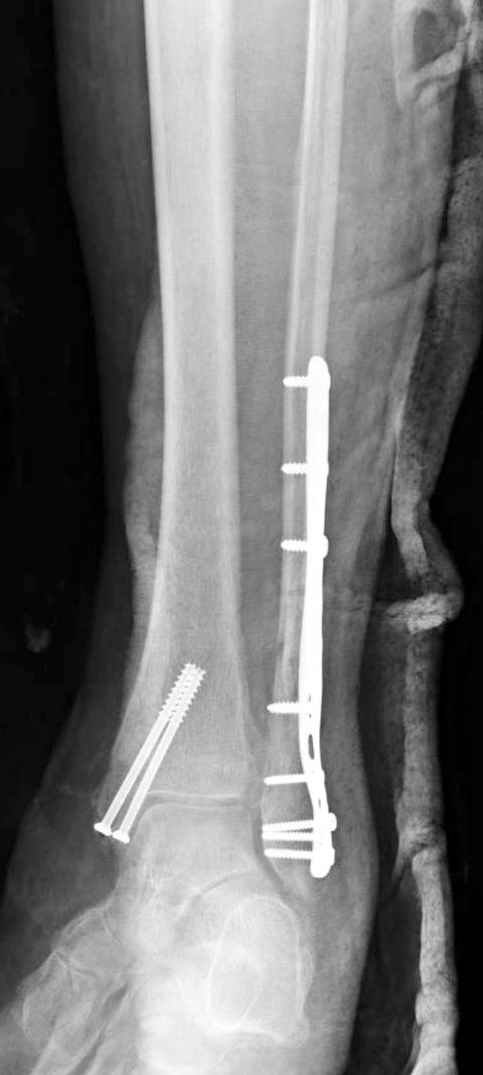

Здесь финальный снимок 73 летней с

сопутствующей шизофренией, латерально бридж

пластину (соединили дистальный конец с диафизом не трогая место перелома) и медиально перкутанно

двумя шурупами. В этам случае без гипса не

обойтись.

Как заметил, по рентгенограмме медиальная лодыжка не очень идеально репонирована. Больная кроме шизофрении страдала другими соматическими заболеваниями, и во время операции от анестезиолога получил рекомендацию поторопиться, поэтому решили закрыто, а так тенденция лечить